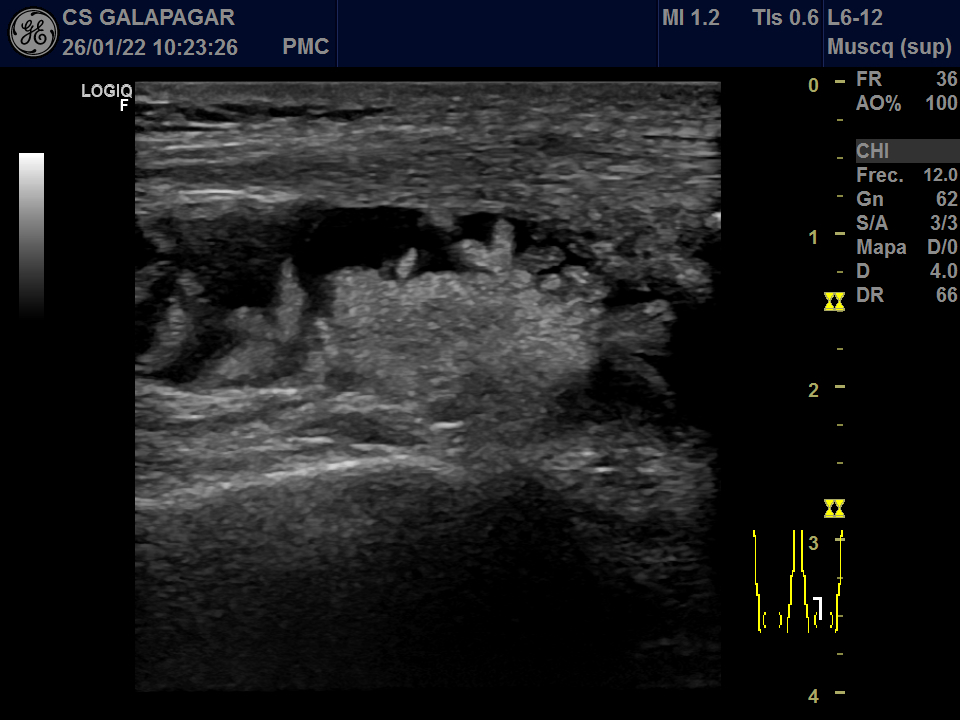

01/22: Abundante derrame en bursa con sinovitis muy proliferativa.